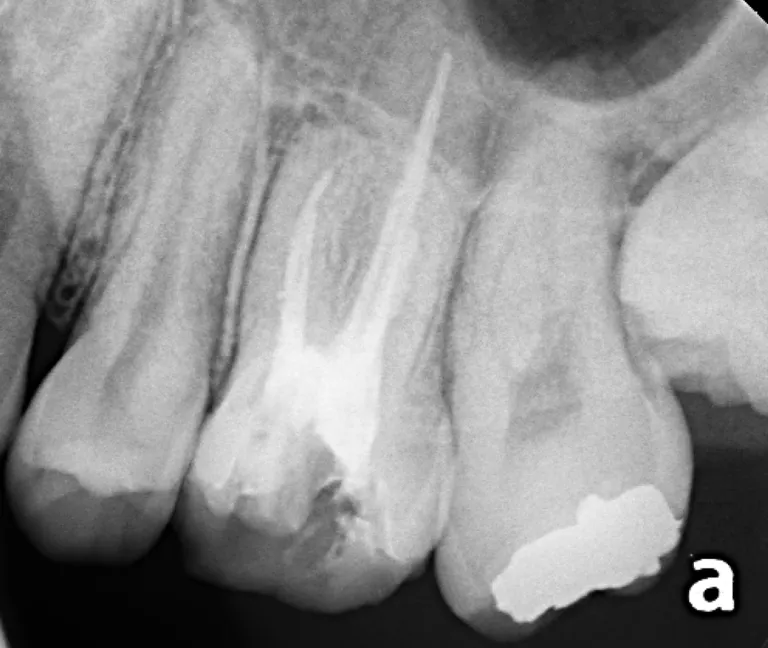

ガッタパーチャというゴムに近い素材とシーラーという流動性の高い素材とで、根っこの中を緊密につめていきます。しっかりつめて余剰な部分を切り取って、仮のフタをしてからレントゲン写真をとります。

レントゲン写真を撮影して、しっかり詰まってることを確認すれば、歯内療法としては一安心

(22歳男性。2024/11/28撮影)

イメージとしてはこのように、根っこに詰めた材料の上に土台(ファイバーコア)を作ります。